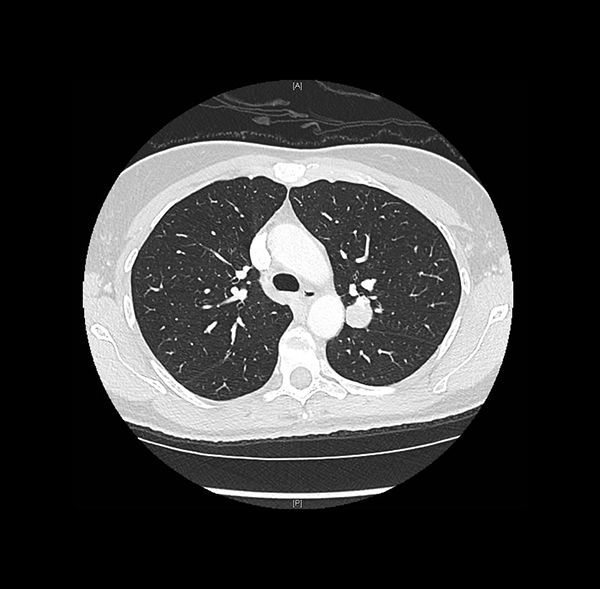

Clinical History: A 47-year-old woman, former smoker, was found to have an incidental lung nodule during the workup of an appendiceal adenocarcinoma ex-goblet cell carcinoid. The chest CT showed a round, well-circumscribed solid nodule in the posterior left upper lobe abutting the major fissure, measuring 2.0 cm (Figure 1). A trans-thoracic core needle biopsy was performed (Figures 2-6; Fig 3: pancytokeratin, Fig 4: epithelial membrane antigen, Fig 5: TTF-1, Fig 6: napsin A).